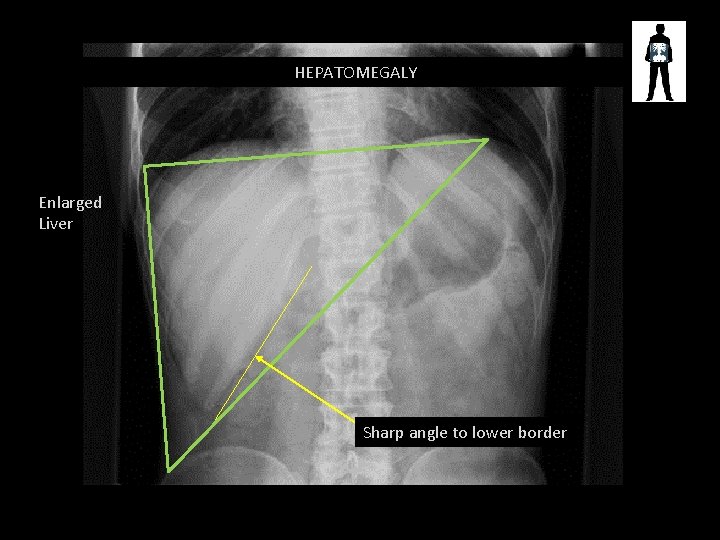

HEPATOMEGALY Enlarged Liver Sharp angle to lower border

Hepatomegaly Enlargement of the liver is usually caused by • Infections – Hepatitis – Glandular Fever (acute) – Cirrhosis • Tumours – – Metastases Liver carcinoma Leukaemia Lymphoma • Disease – congenital problems – drugs/alcohol